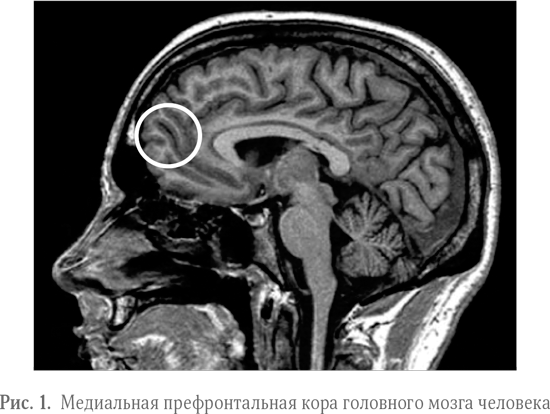

Когда мы с нашими помощниками-студентами подобрали наборы картинок, мы пригласили еще две дюжины студентов того же самого колледжа для проведения сканирования мозга. Эти ребята ничего не знали о нашем эксперименте заранее. К тому же мы никогда не упоминали о том, что эксперимент посвящен крутизне и ее влиянию на ценность продукта, – мы вообще не употребляли слов «крутой» или «крутизна». Все, о чем мы просили участников эксперимента, – просто лежать в томографе и смотреть на изображения, появляющиеся на экране. Лиза Линг и Алан Алда также пришли к нам в лабораторию, чтобы принять участие в исследовании. После сканирования мы выдали всем испытуемым опросники и попросили их расставить увиденные продукты по степени крутизны. Затем мы изучили, как мозг реагирует на крутые предметы. Самым удивительным для нас оказалась активизация медиальной префронтальной коры (МПФК, см. рис. 1).

Насколько то или иное событие или объект значимы для вас, зависит от того, отражают ли они ваше чувство собственного «я», внутреннюю модель вашей личности, в том числе и то, как вы сами воспринимаете свой характер, вкусы, предпочтения, физические особенности, умения и т. д. Если вы когда-нибудь находили себе новое хобби, например кататься на велосипеде, и после этого вдруг начинали замечать велосипедистов повсюду, это не потому, что вы основали новый тренд, который все копируют. Просто велосипеды теперь имеют к вам отношение. Аналогичным образом товары, отражающие ваше чувство собственного «я», более значимы для вас. Поэтому лишь некоторые из товаров привлекают ваше внимание, когда вы ходите по магазинам или пролистываете журнал. Именно поэтому в нашем эксперименте у Алана, Лизы и студентов-дизайнеров МПФК активизировалась сильнее всего при взгляде на товары, которым после сканирования они присвоили самый высокий рейтинг крутизны. Медиальная префронтальная кора отслеживала значимость товаров для их чувства собственного «я».